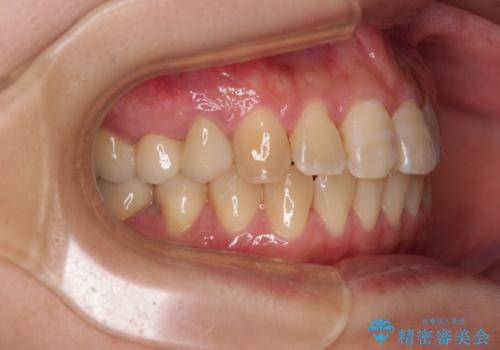

治療の期間と費用はかかりますが、初診時とは比べものにならないほど良好な状態にて治療を終えることができました。